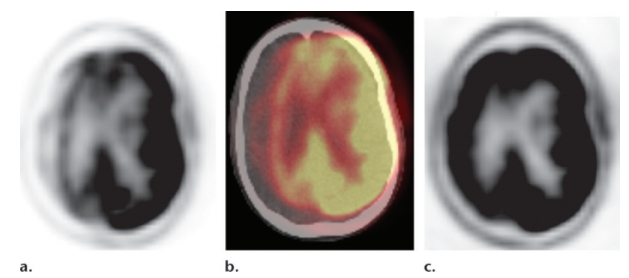

If the frontal lobe or internal capsule is involved, hypometabolism in the contralateral cerebellum may be seen due to crossed cerebrocerebellar diaschisis

misregistration due to patient motion

atrophy –> sulcal widening –> artifact of hypometabolism (pitfall for misdiagnosis of neurodegenerative disorder)